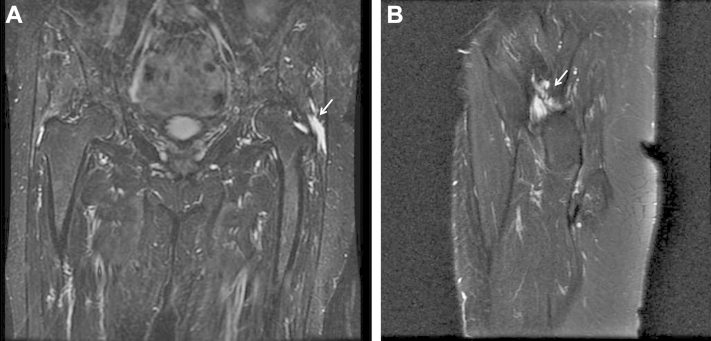

Initial treatment should consist of a trial of conservative management including nonsteroidal anti-inflammatory drugs and physical therapy focusing on range of motion and abductor strengthening. Pain that is recalcitrant to corticosteroid injections and other nonoperative treatment may be further evaluated with advanced imaging. Ultrasound may identify thickening or fluid signals with 79% sensitivity and a nearly 100% positive predictive value,9 but it is highly user dependent. MRI allows differentiation between partial- and full-thickness tears and may also be used to characterize the degree of tendon calcification and fatty atrophy. Partial or complete defects are best visualized as a hyperintense signal on T2-weighted MRI (Fig 1), whereas T1-weighted sequences are best for identifying the degree of fatty degeneration (Fig 2). When a tear is visible on MRI, surgical repair should be considered early to impede gradual degeneration.8

Fig 1.

(A) T2-weighted coronal magnetic resonance image of the pelvis showing a full-thickness gluteus medius tear (arrow) of the left hip. (B) T2-weighted sagittal series may be used to estimate the amount of tendon retraction (arrow).